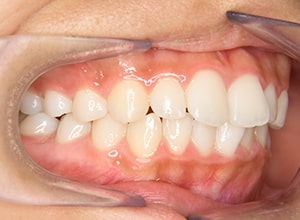

| 口腔内所見 | over jet 3.5mm,over bite4.0mm、下顎正中右側偏位2.0mm、大臼歯関係は左側Ⅰ級であったが、右下6は右下E早期喪失のため近心傾斜しておりⅢ級の臼歯関係となっていた。また上下顎前歯は軽度の叢生を呈していた。 |

| 批評・予后 | 右下5及び7の萌出前に右下6を整直させることによって、右下5の自然萌出が可能となり正常咬合への咬合誘導が行えたと思う。 |